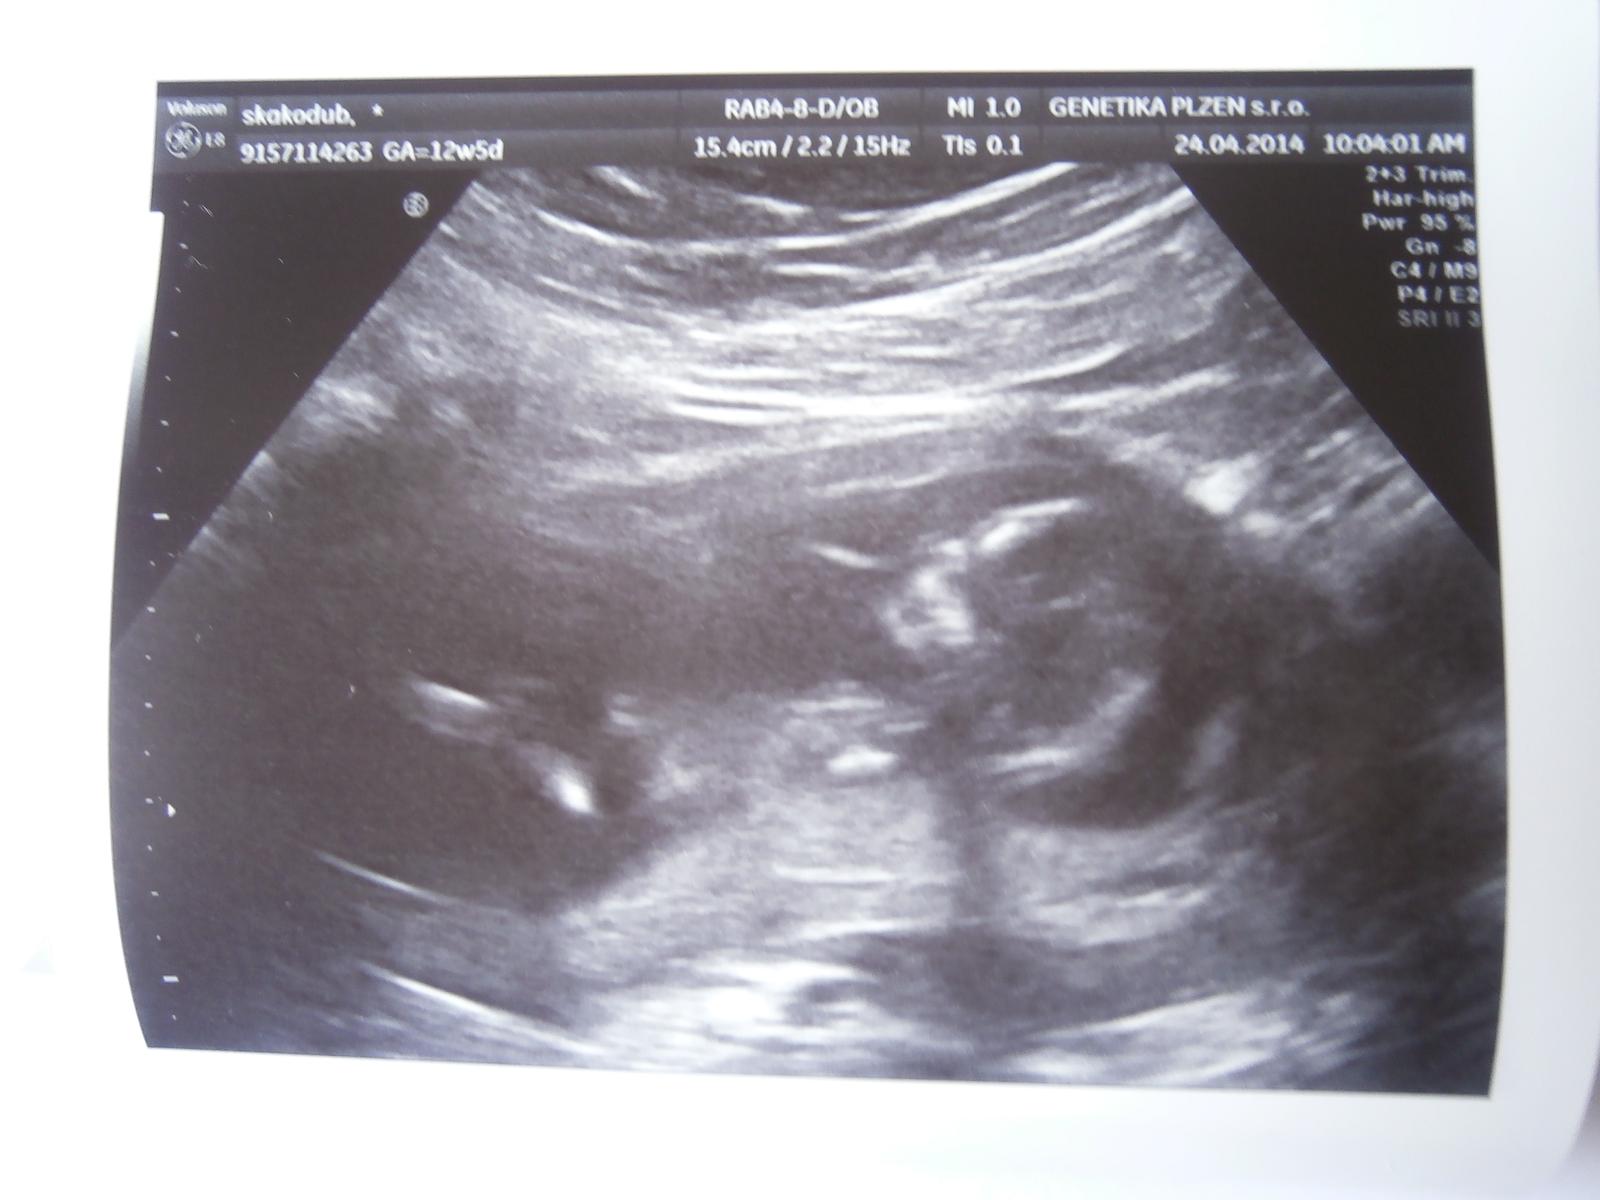

@ynett to teda je zlatičko 🙂 se nedivim že občas mi příjde kdybych ho citěla, včera jak jsem šla spat tak takové šimrani vedle u pupiku ale rikala jsem si že to neni možne, no a jak jsem ho dneska viděla prdolku malou😀 pochybnosti ustupuji.